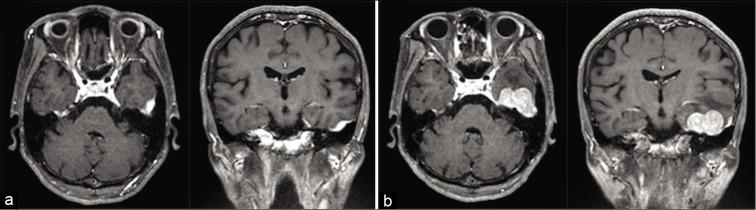

Intracranial and central nervous system's involvement with multiple myeloma (MM) is a clinically rare manifestation. Furthermore, the development of intracranial plasmacytoma without bone involvement is much rarer. Herein, we report the case of massive intracerebral hemorrhage form intracranial plasmacytoma that arose from the dura mater without bone involvement.

A 71-year-old woman, who had been diagnosed as MM and treated 2 years prior, developed sudden lethal intracerebral hemorrhage from the intracranial plasmacytoma. Massive hemorrhage was observed after a rapid tumor growth in the middle fossa. Immediate hematoma evacuation and tumor resection allowed the patient to avoid severe neurological deficits and lethal conditions.

颅内及中枢神经系统受累于多发性骨髓瘤(MM)是一种临床罕见的表现。此外,无骨受累的颅内浆细胞瘤的发生更为罕见。在此,我们报告一例起源于硬脑膜且无骨受累的颅内浆细胞瘤导致大量脑出血的病例。

一名71岁女性,2年前被诊断为MM并接受治疗,因颅内浆细胞瘤突发致死性脑出血。中颅窝肿瘤快速生长后出现大量出血。立即进行血肿清除和肿瘤切除使患者避免了严重的神经功能缺损和致命情况。